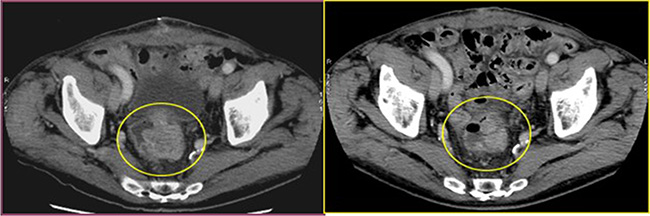

All patients experienced local disease control; in 4/12 cases (33%) we observed an outstanding radiological response with a dramatic reduction in the tumor size which led us to radical surgical resection. (Figures 1, 2, 3). Main result of the volume change is summarized in the Table 2. The Only patient who required DEBIRI twice achievied stable disease.

Figure 2: Cross section of contrast enhanced CT scan of the pelvis (venous phase). Left image: into the yellow circle tumor before chemoembolisation; Right image : into the yellow circle the reduction size of the lesion (30 day after treatment).